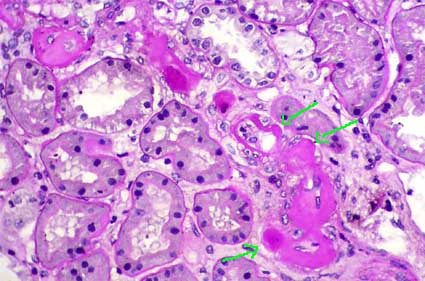

Glomerulopatía crónica del trasplante: Se caracteriza morfológicamente por dobles contornos en las paredes capilares. Esta lesión se debe a síntesis de material similar al de la MBG, en su parte interna y con interposición de células en muchos de los casos. Su patogénesis no está clara; parece que una agresión inmune repetida o continua al endotelio capilar genera, de alguna manera, este cambio. Se gradúa de acuerdo a su extensión en los glomérulos más severamente afectados (Tabla 11). Esta lesión se considera ahora asociada (o debida a) rechazo crónico mediado por anticuerpos (Solez K, et al. Am J Transplant 7:518-526 [Abstract link])

Figura 15. La glomerulopatía crónica del trasplante es uno de los marcadores histológicos que sugiere rechazo crónico (mediado por anticuerpos). Se caracteriza por imágenes en doble contorno de las paredes capilares (flechas). Podemos ver aspecto irregular de la MBG y células mesangiales interpuestas entre estos dos contornos. Esta lesión se gradúa, de acuerdo al esquema de Banff, según la extensión del comrpomiso en los glomérulos más afectados (Tabla 8). (Plata-metenamina, X400).